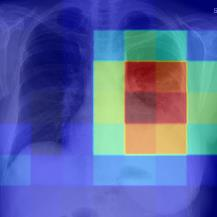

Thoracic disease detection from chest radiographs using deep learning methods has been an active area of research in the last decade. Most previous methods attempt to focus on the diseased organs of the image by identifying spatial regions responsible for significant contributions to the model's prediction. In contrast, expert radiologists first locate the prominent anatomical structures before determining if those regions are anomalous. Therefore, integrating anatomical knowledge within deep learning models could bring substantial improvement in automatic disease classification. This work proposes an anatomy-aware attention-based architecture named Anatomy X-Net, that prioritizes the spatial features guided by the pre-identified anatomy regions. We leverage a semi-supervised learning method using the JSRT dataset containing organ-level annotation to obtain the anatomical segmentation masks (for lungs and heart) for the NIH and CheXpert datasets. The proposed Anatomy X-Net uses the pre-trained DenseNet-121 as the backbone network with two corresponding structured modules, the Anatomy Aware Attention (AAA) and Probabilistic Weighted Average Pooling (PWAP), in a cohesive framework for anatomical attention learning. Our proposed method sets new state-of-the-art performance on the official NIH test set with an AUC score of 0.8439, proving the efficacy of utilizing the anatomy segmentation knowledge to improve the thoracic disease classification. Furthermore, the Anatomy X-Net yields an averaged AUC of 0.9020 on the Stanford CheXpert dataset, improving on existing methods that demonstrate the generalizability of the proposed framework.